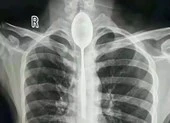

Chiếc chìa khóa có gắn móc nhựa được lấy ra sau đó. Ảnh: ODD

Sau khi bác sĩ gây mê cho Chang sử dụng một loại thuốc giúp giãn cơ, bác sĩ tiêu hóa đã có thể rút chìa chìa khóa kim loại và tấm thẻ gắn kèm bằng nhựa ra khỏi thực quản chàng trai.